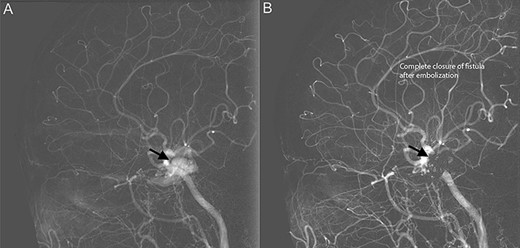

Diagnostic cerebral angiogram demonstrative of right indirect CCF. (A) Right ICA angiogram revealed indirect fistulization between the ECA branches and cavernous sinus (type D CCF) (B) with subsequent successful endovascular coil embolization.

Diagnostic cerebral angiogram (DCA) revealed bilateral indirect CCFs (type D on the right, type B on the left) with significantly higher flow on the right compared to the left (Figs 1C, 2A, 3A). A day later, through micro puncture of the right common femoral artery, coil was advanced (under real-time sonographic guidance and DCA). A microcatheter was used to access the right cavernous sinus via the left cavernous sinus through the intercavernous sinus. Right indirect CCF with arterial feeders arising from both the internal and external carotid arteries with outflow through the intercavernous sinus was confirmed. Embolization of the right cavernous sinus and intercavernous sinus was performed with 11 detachable coils and resolution of the type D carotid-cavernous flow was immediately noted (Fig. 2B); spontaneous resolution of the left type B CCF was noted (Fig. 3B) over a 24-h period of time.